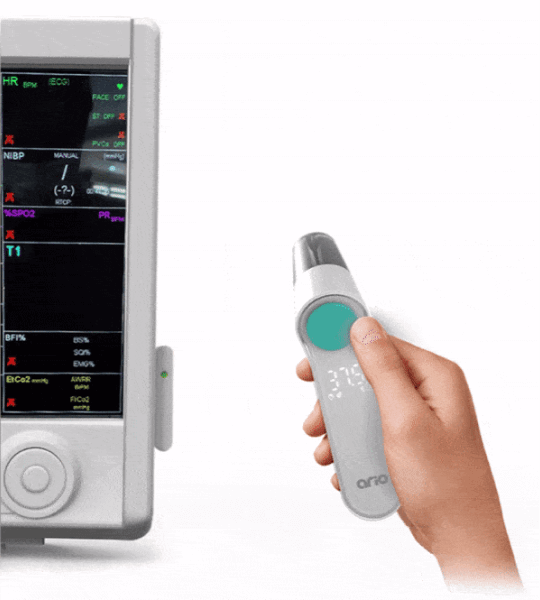

بیش از 250 بیمارستان به آریو اعتماد کرده اند

دماسنج هوشمند غیرتماسی آریو

اندازهگیری دقیق در کمتر از ۲ ثانیه، مطابق با استانداردهای اتحادیه اروپا.

بیش از 250 بیمارستان به آریو اعتماد کرده اند